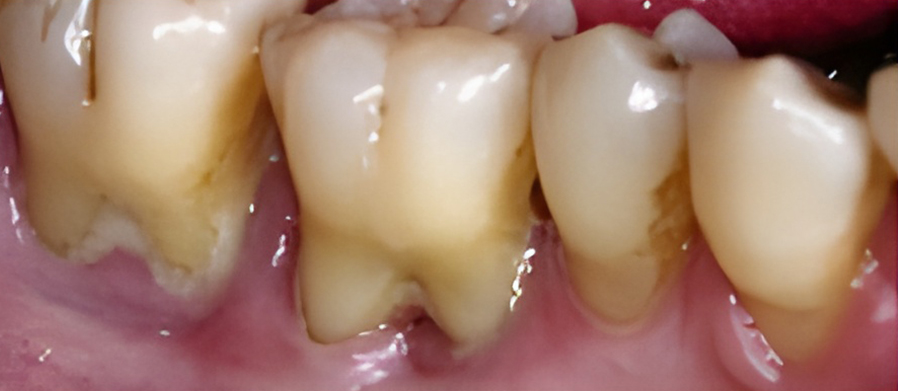

When a tooth decays and becomes damaged, several treatment options are available depending on the size and severity of the cavity. The most common cavity treatments are as follows:

For relatively small to mid-sized cavities, a composite resin filling is recommended. It is made of a plastic resin reinforced with powered glass, allowing for a color match to the surrounding teeth.

Only one visit is required for this treatment.

When the cavity is too big for a composite resin filling, an inlay is recommended. It is a fabricated, custom-fit restoration and can be made of porcelain or gold.

While a gold inlay takes two visit, a porcelain inlay takes only one visit, thanks to the use of a CEREC CAD/CAM milling machine.